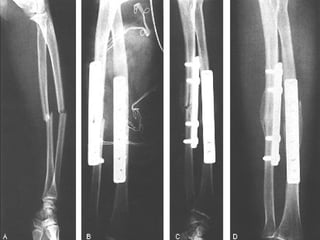

CLASIFICACION Las clasificaciones complementarias se basan en el grado de lesión de partes blandas, siendo la mas utilizada la de Gustilo

CLASIFICACION DE GUSTILLO I:  Herida < 1 cm. Herida limpia realizada por un fragmento puntiagudo de hueso que perfora la piel, existe escasa lesión a tejidos blandos, sin signos de aplastamiento, son por baja energía

CLASIFICACION DE GUSTILLO II:  Longitud > 1 cm. Sin colgajos, avulsiones y sin una gran lesión de tejido blando, existe un mínimo a moderado aplastamiento, conminución y contaminación moderada

CLASIFICACION DE GUSTILLO III:  Lesión extensa de tejidos blandos que afectan al músculo, piel y estructuras neurovasculares, suele existir un alto grado de contaminación, son por alta energía A)  cobertura adecuada de tejido blando del hueso, sin importar el tamaño de la herida

CLASIFICACION DE GUSTILLO B)  Afectación extensa o perdida del tejido blando con exposición del hueso, contaminación masiva y una grave fractura conminuta C)  Se asocia a lesión arterial  que necesita reparación independientemente del grado de lesión del tejido blando

CLASIFICACION Las clasificacionescomplementarias se basan en el grado de lesión de partes blandas, siendo la mas utilizada la de Gustilo

CLASIFICACION DE GUSTILLOI: Herida < 1 cm. Herida limpia realizada por un fragmento puntiagudo de hueso que perfora la piel, existe escasa lesión a tejidos blandos, sin signos de aplastamiento, son por baja energía

CLASIFICACION DE GUSTILLOII: Longitud > 1 cm. Sin colgajos, avulsiones y sin una gran lesión de tejido blando, existe un mínimo a moderado aplastamiento, conminución y contaminación moderada

CLASIFICACION DE GUSTILLOIII: Lesión extensa de tejidos blandos que afectan al músculo, piel y estructuras neurovasculares, suele existir un alto grado de contaminación, son por alta energía A) cobertura adecuada de tejido blando del hueso, sin importar el tamaño de la herida

CLASIFICACION DE GUSTILLOB) Afectación extensa o perdida del tejido blando con exposición del hueso, contaminación masiva y una grave fractura conminuta C) Se asocia a lesión arterial que necesita reparación independientemente del grado de lesión del tejido blando